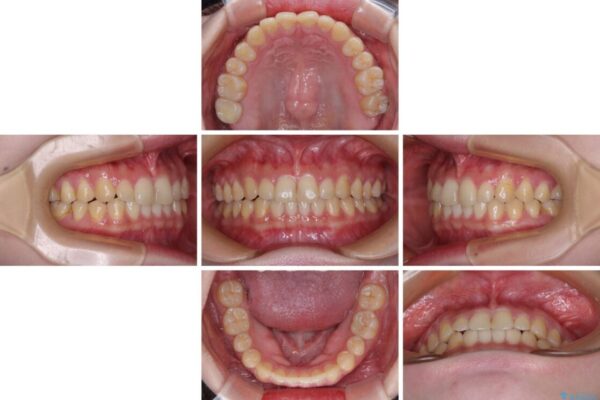

根管治療を行ったままの奥歯と、矯正治療の後戻りを気にして来院された患者様です。

矯正治療の後戻りは軽微であったため、インビザラインの簡易パッケージであるインビザライン・ライトを用いて歯列を整えることとしました。

クラウンはよりよい咬み合わせで装着したいため、インビザラインを1セット使用して概ね歯列を整えた時点で補綴治療を行い、その後仕上げの矯正治療を行いました。

治療前

治療後

• 治療途中の奥歯と矯正治療の後戻り インビザライン・ライトによる矯正治療 治療後画像